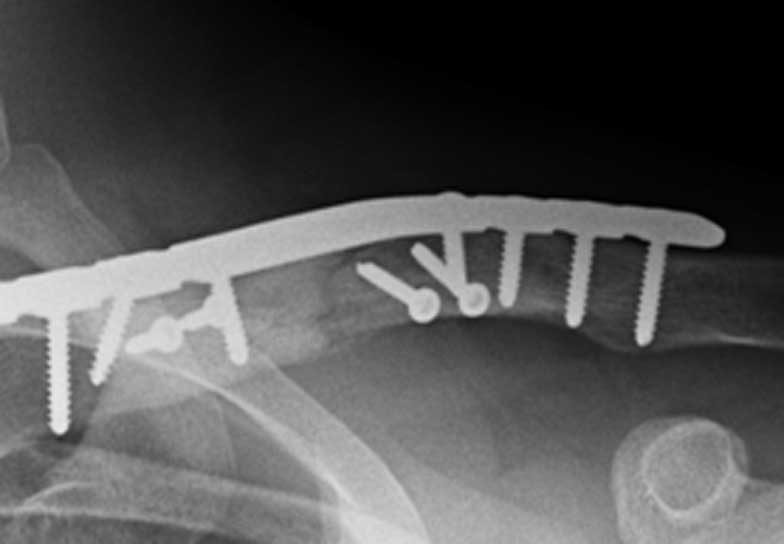

In my practice and what is generally becoming more accepted in the literature, is that most fractures of the clavicle that are displaced, angulated or overlapped are best treated with an operation. This operation can either be performed by realigning the bones in their original shape using a plate and screws on top of the bone or by using a pin that goes down the centre of the bone. Both of these techniques are successful and the decision generally comes down to the fracture pattern and the preference of the surgeon. The idea of the operation is to make the patient as comfortable as possible by making the fracture stable, and therefore allowing the patient to return to normal activities as soon as possible.

Generally all displaced fractures of the distal clavicle require surgery to increase the incidence of union. In my practice, the operation is performed by realigning the bones back to their original position using a plate and screws on top of the bone. The advantage of fixing them with a plate and screws generally means that you can start to move the arm a lot quicker and to also decrease the incidence of non-union.

How is the Operation Done?

The operation is performed with the patient under a general anaesthetic, in other words, completely asleep, and a small 3-4 cm incision is made under the collarbone, at the end of the shoulder. The fractured bone ends are exposed and put back into position using a plate and screws as shown below.

Click an image to enlarge

A 15 year old female fell from her pushbike causing a displaced left mid-shaft clavicular fracture. Seen 5 days later, plate & screws inserted 2 days later.

DIsplaced fracture after surgery

Move the slider to compare before surgery and after surgery